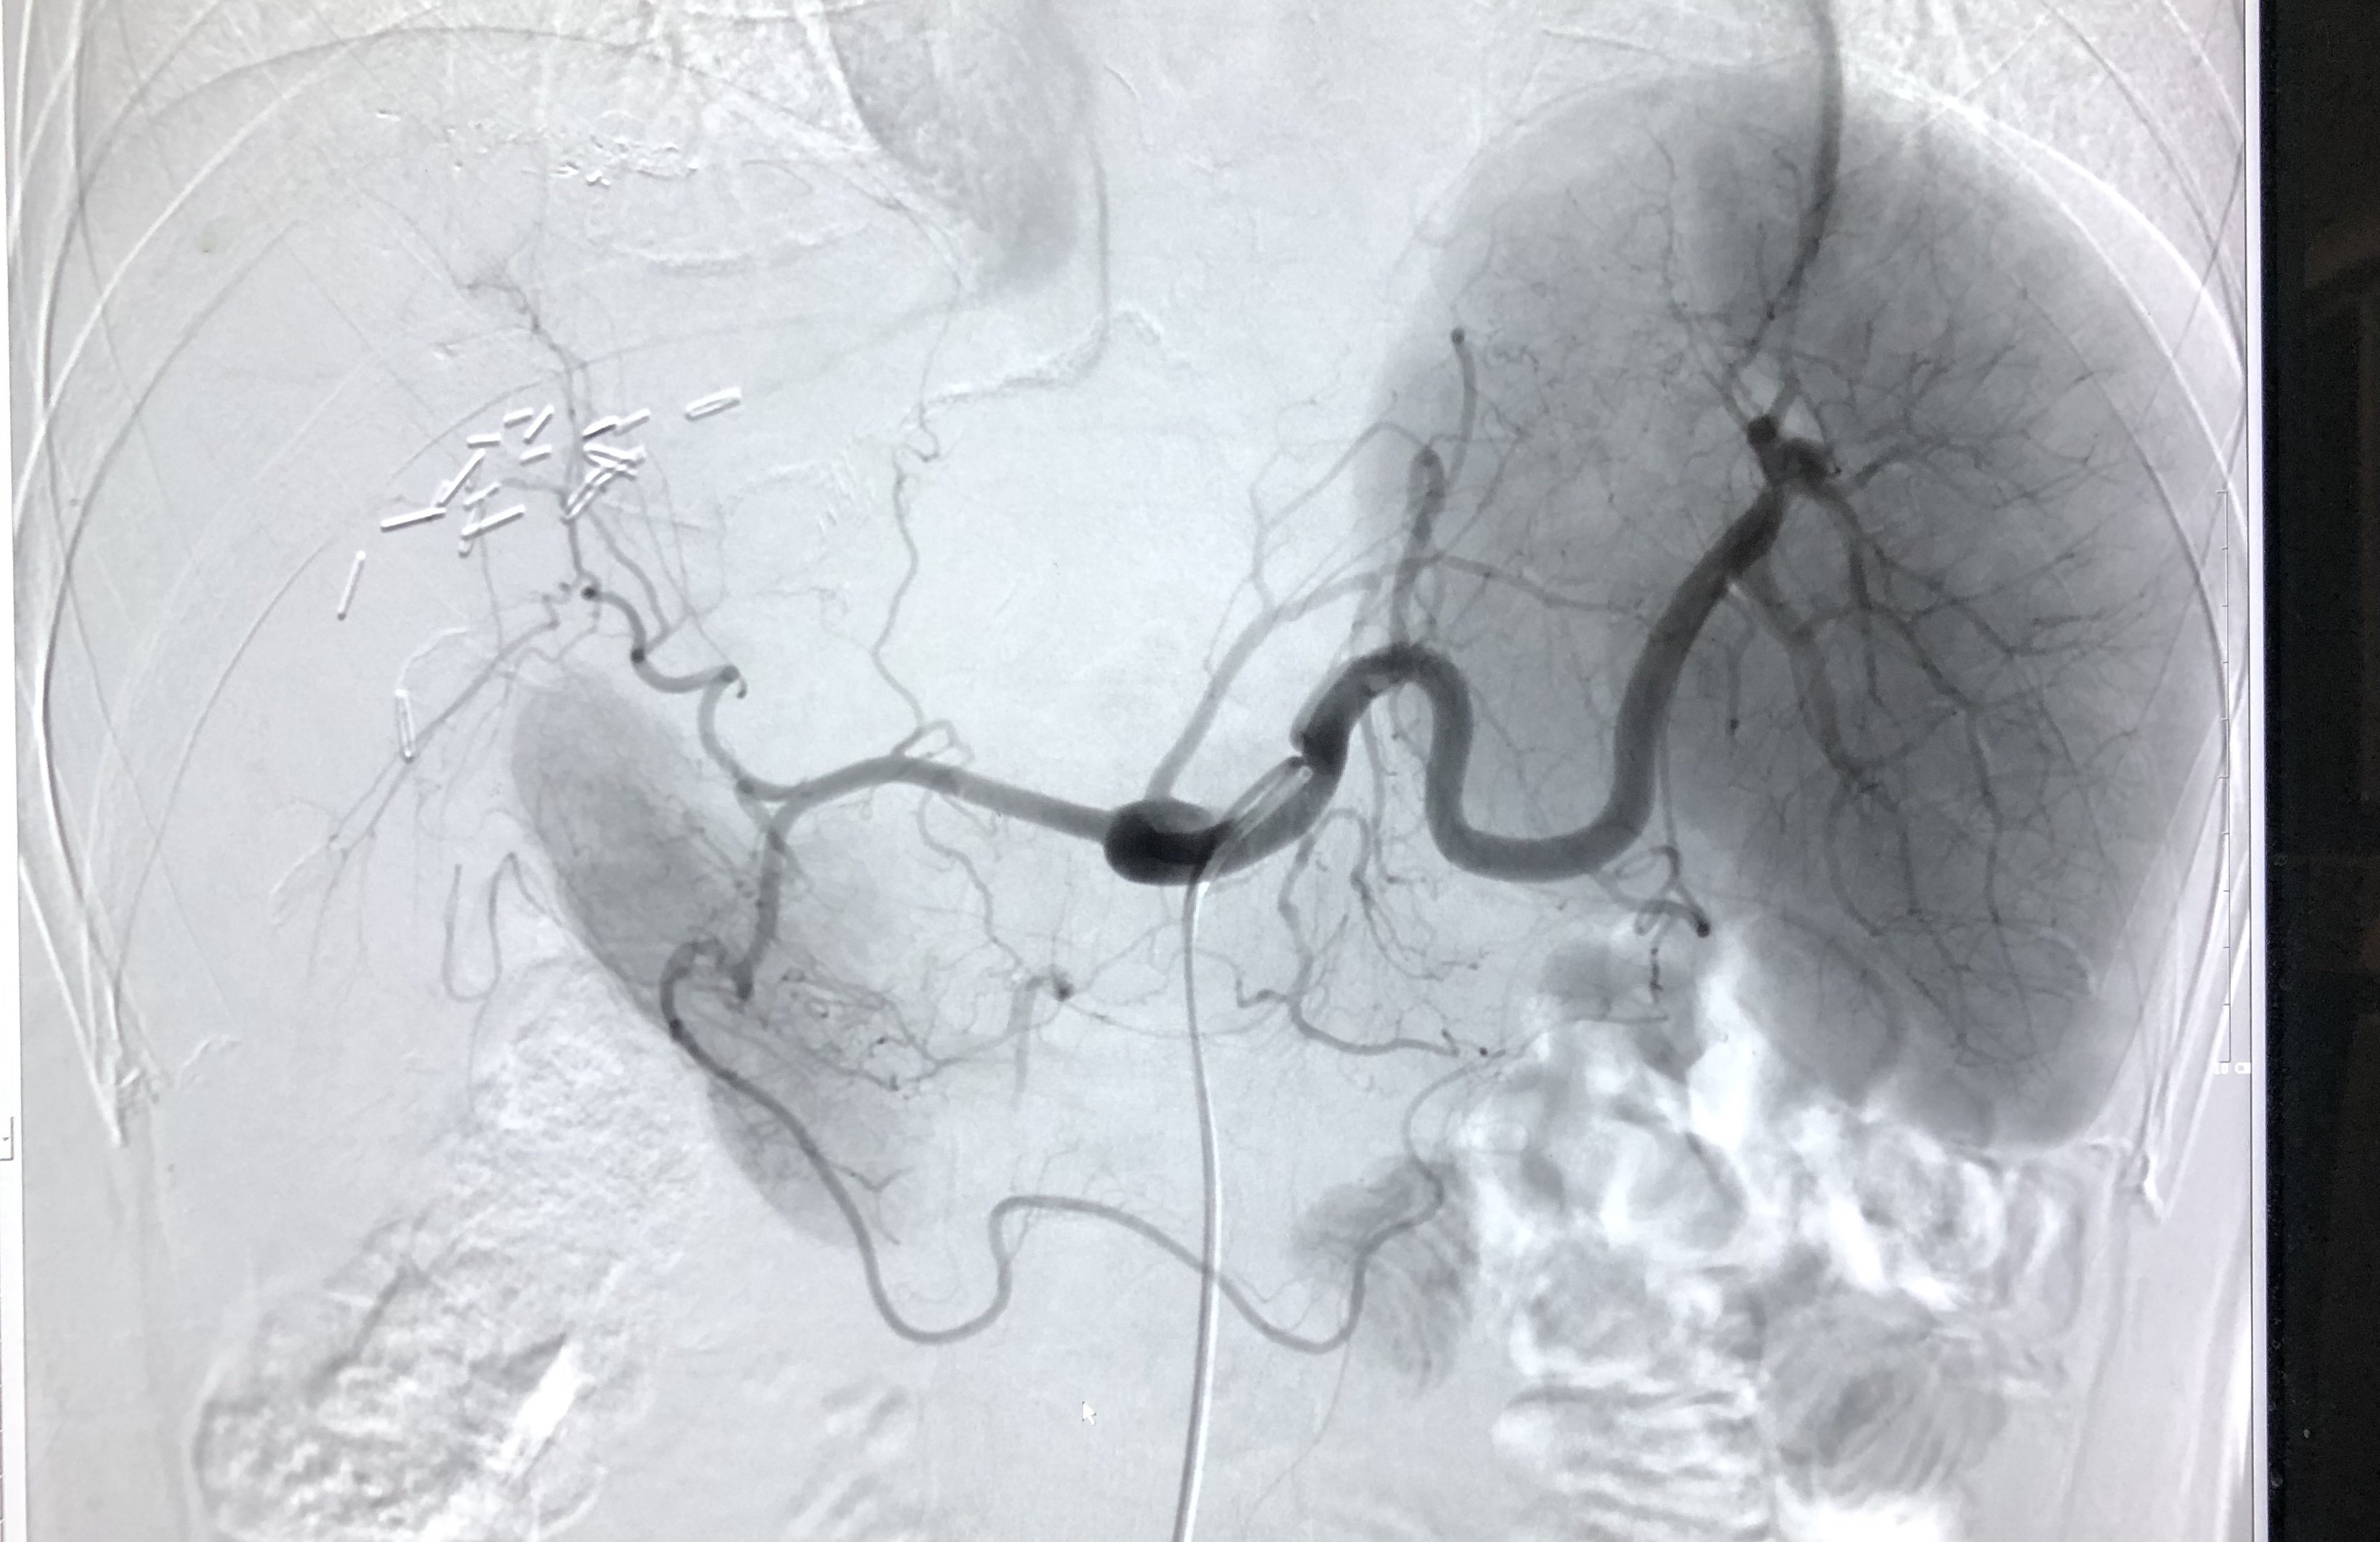

肝动脉造影图片

肝动脉造影,肝门区见肝血管瘤影像